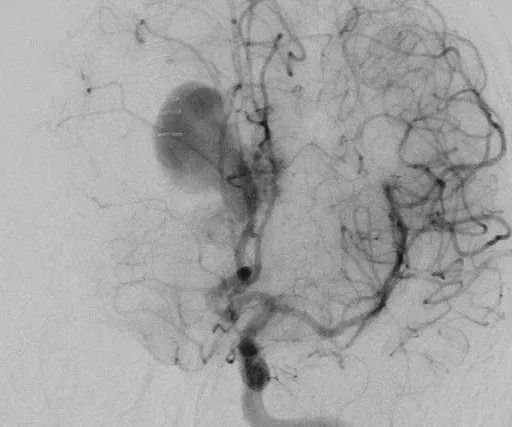

他紧急行半侧颅骨切除术,随后血管造影显示右侧动脉瘤,AVM由双侧PcaA供血,引流向前MedFrV和SplenV【左侧ICA像,(a)前后位(b)侧位】(c)首先通过双侧开颅并排夹闭动脉瘤(鼻朝右,中线呈水平,重力牵开右侧额叶),然后切开动脉瘤使之缩小。

患者案例2:17岁男孩,表现为来自于右侧胼胝体压部AVM的脑室内出血(补充Spetzler-Martin分级4级:S1V1E1/A1B0C0),SplenA供血,SplenV和内侧AtrV引流右椎动脉造影。